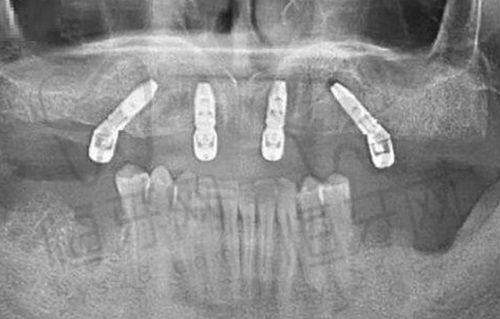

天津海德堡联合口腔以德系技术为特色,它的ALL - ON - 4技术在天津口腔界可是小有名气。这项技术能为全口或半口缺牙患者提供快速、有效的修复方案。

特色亮点:

- 引进德国精良的口腔设备和技术,让患者享受到国内外名列前茅的口腔治疗。

- 医生团队经过德国专精培训,技术不错,经验多。